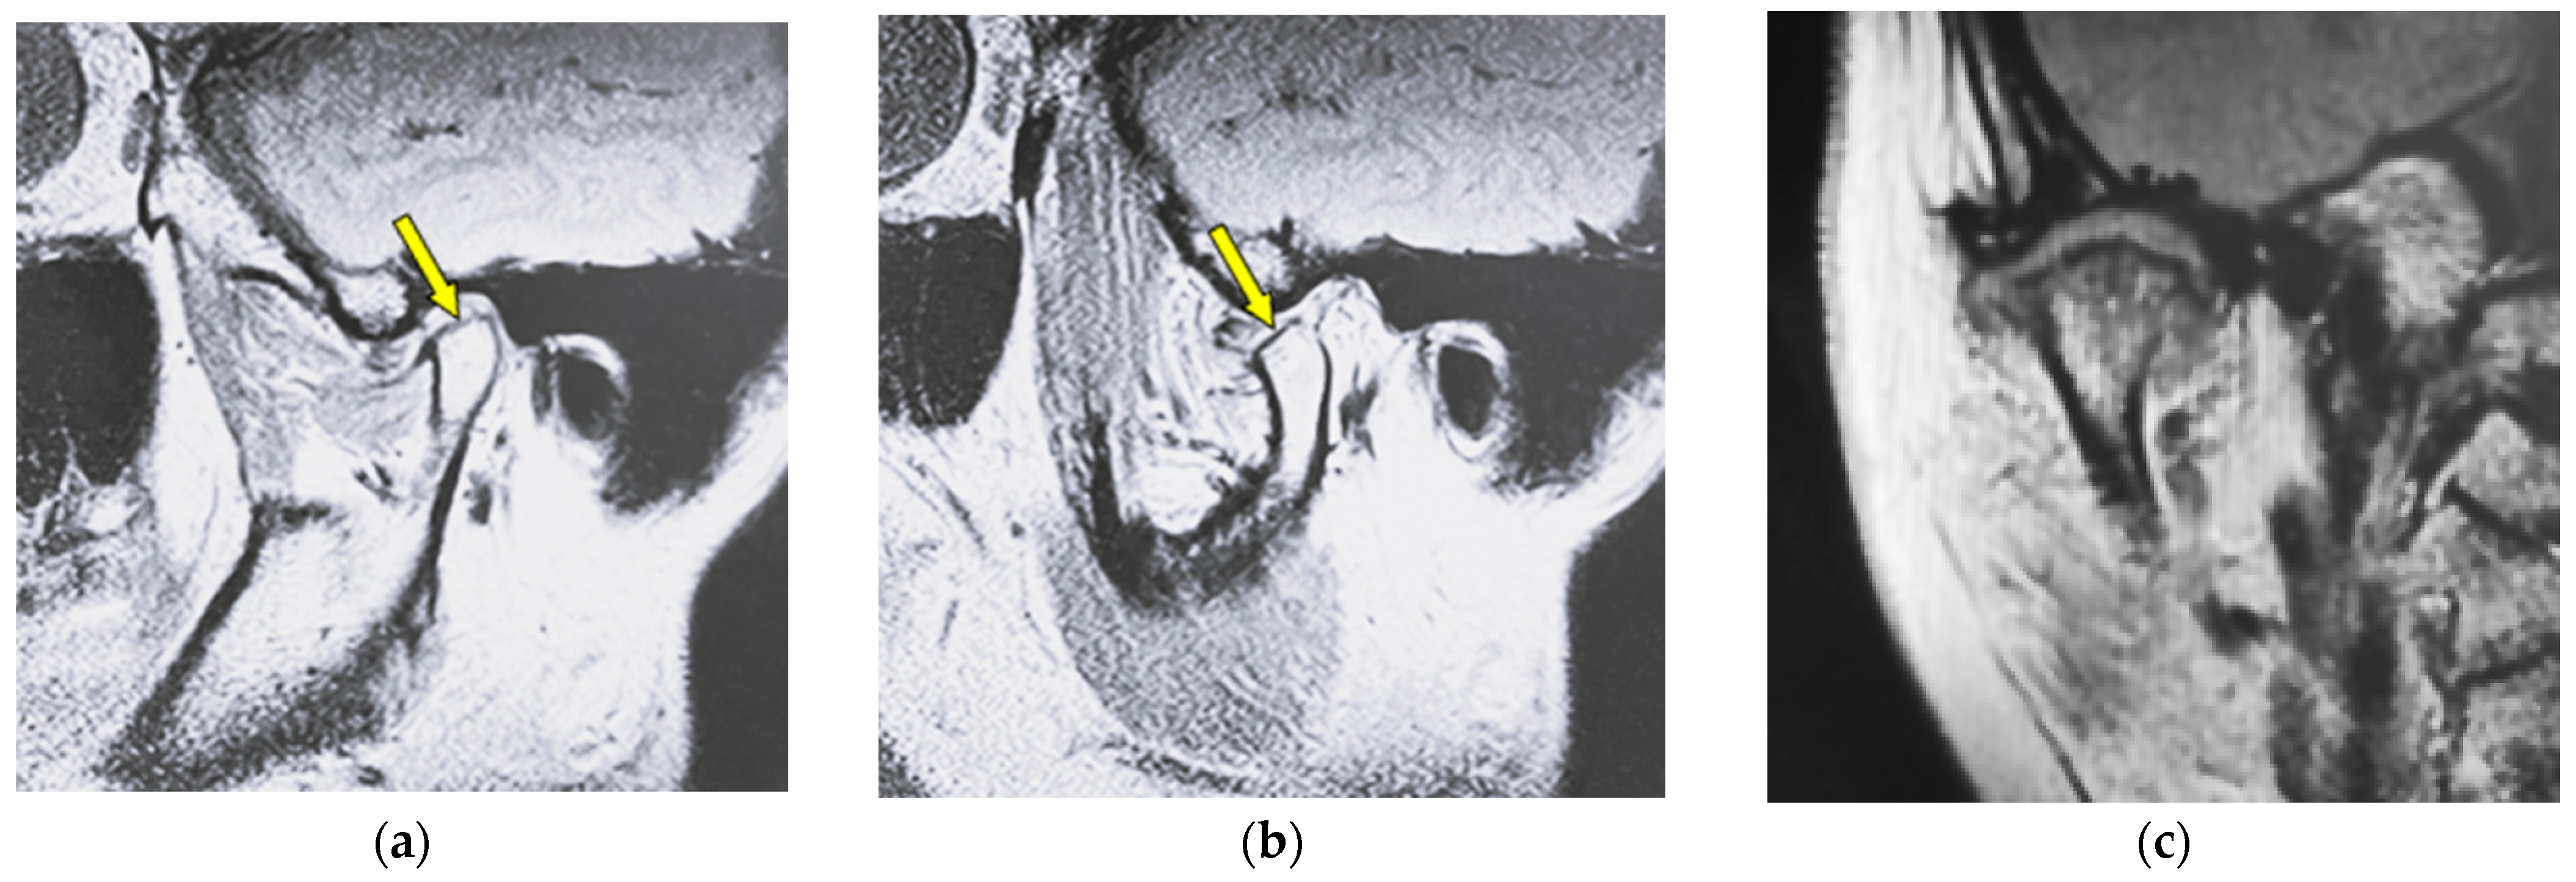

| Flattening | Loss of convexity of the condylar head outline and keeping the cortical bone continuously |